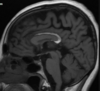

Qual é o padrão de Chiari I

A

Deslocamento caudal das tonsilas cerebelares > 6 mm (infância) Associação com Hidro-siringomielia 70%